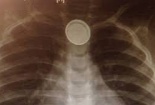

[VIDEO]Trẻ có thể tử vong do... pin cúc áo